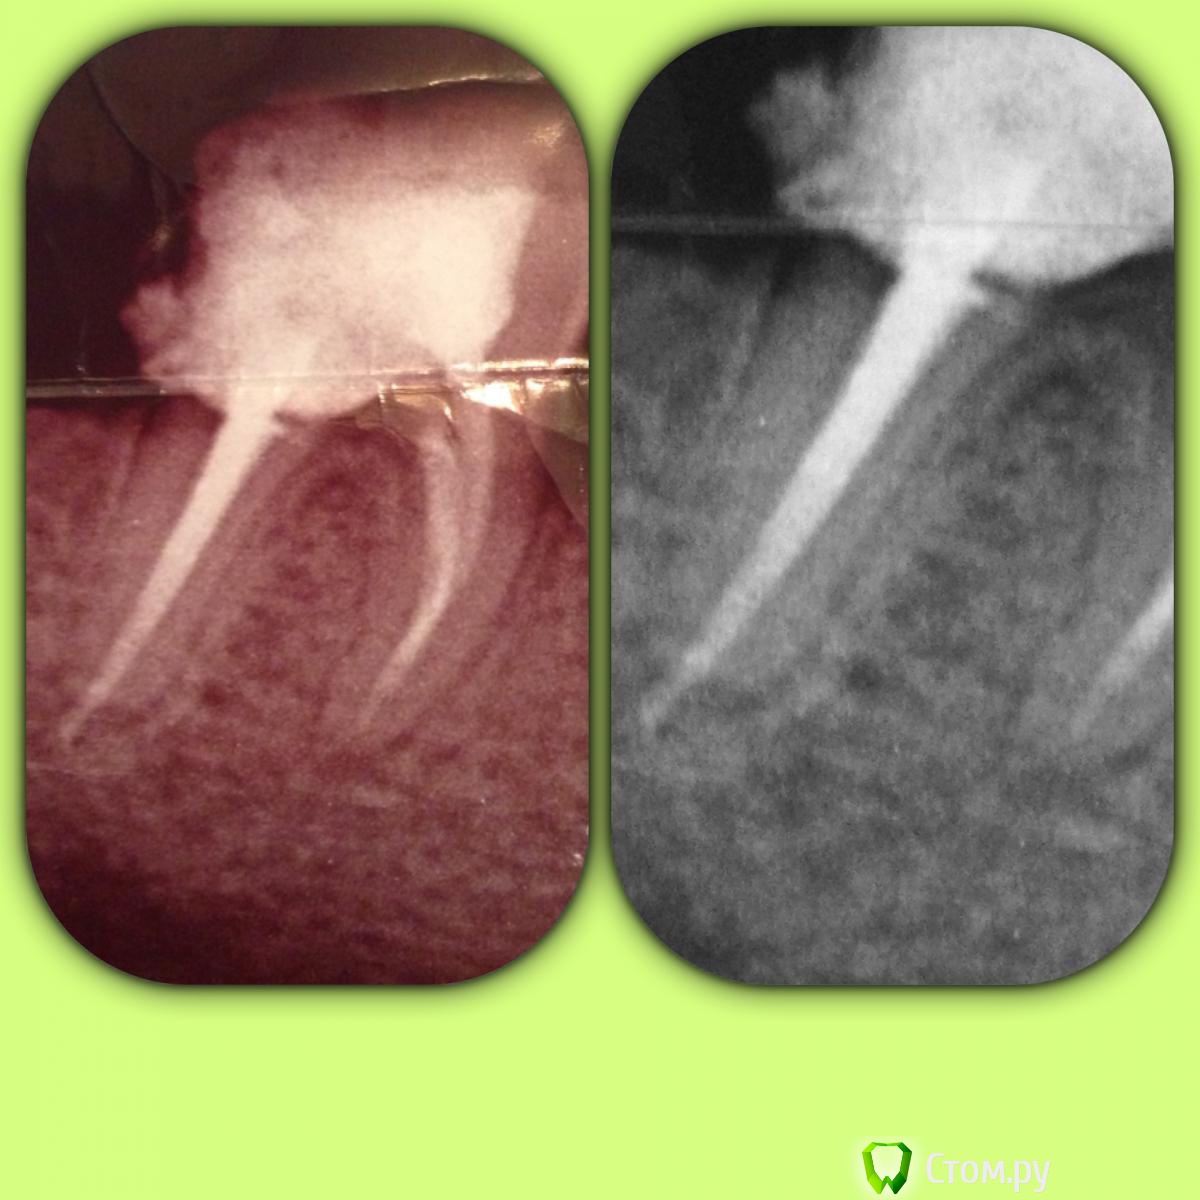

SSTi Опубликовано 23 июня, 2014 Автор Поделиться Опубликовано 23 июня, 2014 Зуб мамы. Июнь 2013. 46. Снимка до нет. Потерял где-то. Пломба дистально была разрушена. Глубокий кариес, леченый много лет назад, стал периодонтитом. Нашел 4 канала. 2 дистальных сходятся. По дурости и молодости в дистальном штифт(мой косяк). Сегодня сделал снимок. Вроде динамика на медиальном лучше, чем на дистальном... Планируем достать штифт, сделать вкв и коронку. Но. Зуб немного реагирует (очень редко) на горячее. Лечил как положено(коффер, хлорка и т.д.). В общем вопрос вот в чем. Лезть в каналы перед вкв или нет? Ссылка на комментарий

faity Опубликовано 23 июня, 2014 Поделиться Опубликовано 23 июня, 2014 межкорневое смотрел, на болезненность? на старом снимке есть затемнение, на новых тоже. Ссылка на комментарий

faity Опубликовано 23 июня, 2014 Поделиться Опубликовано 23 июня, 2014 Перфо не было никаких точно.не, дружище, я не про перфо, я про кость в межкорневой перегородке, затемнение небольшое есть, а раз нерва нет, а чувствительность есть- ищи проблему в пародонте Ссылка на комментарий